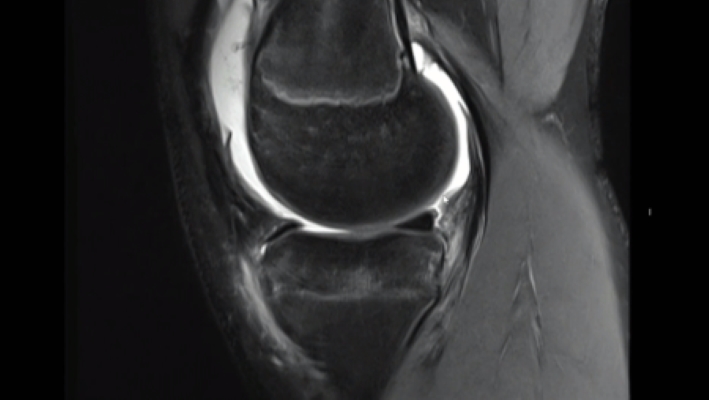

Erkenntnisse zur Wirkung der Produktdosis bei Autologer Chondrozytentransplantation bei Knorpeldefekten im Kniegelenk – Überblick der CO.DIS-Studie

Knorpelzelltranplantation an der Patella vs. Femur - Klinische Ergebnisse und Erfolgsraten im Vergleich

Vorteile der Autologen Chondrozytentransplantion mit Spheroid-Technologie vs. Mikrofrakturierung – Ergebnisse einer Nicht-Unterlegenheitsstudie nach 36 Monaten (CO.WISI)

Sicherheit und Wirksamkeit der Autologen Chondrozytentransplantation bei Jugendlichen im Vergleich zu jungen Erwachsenen (PIP-Studie)

Wichtigste Studienergebnisse aus dem Zulassungsprozess des Produktes Spherox für die zentrale europäische Zulassung – Überblick und Diskussion